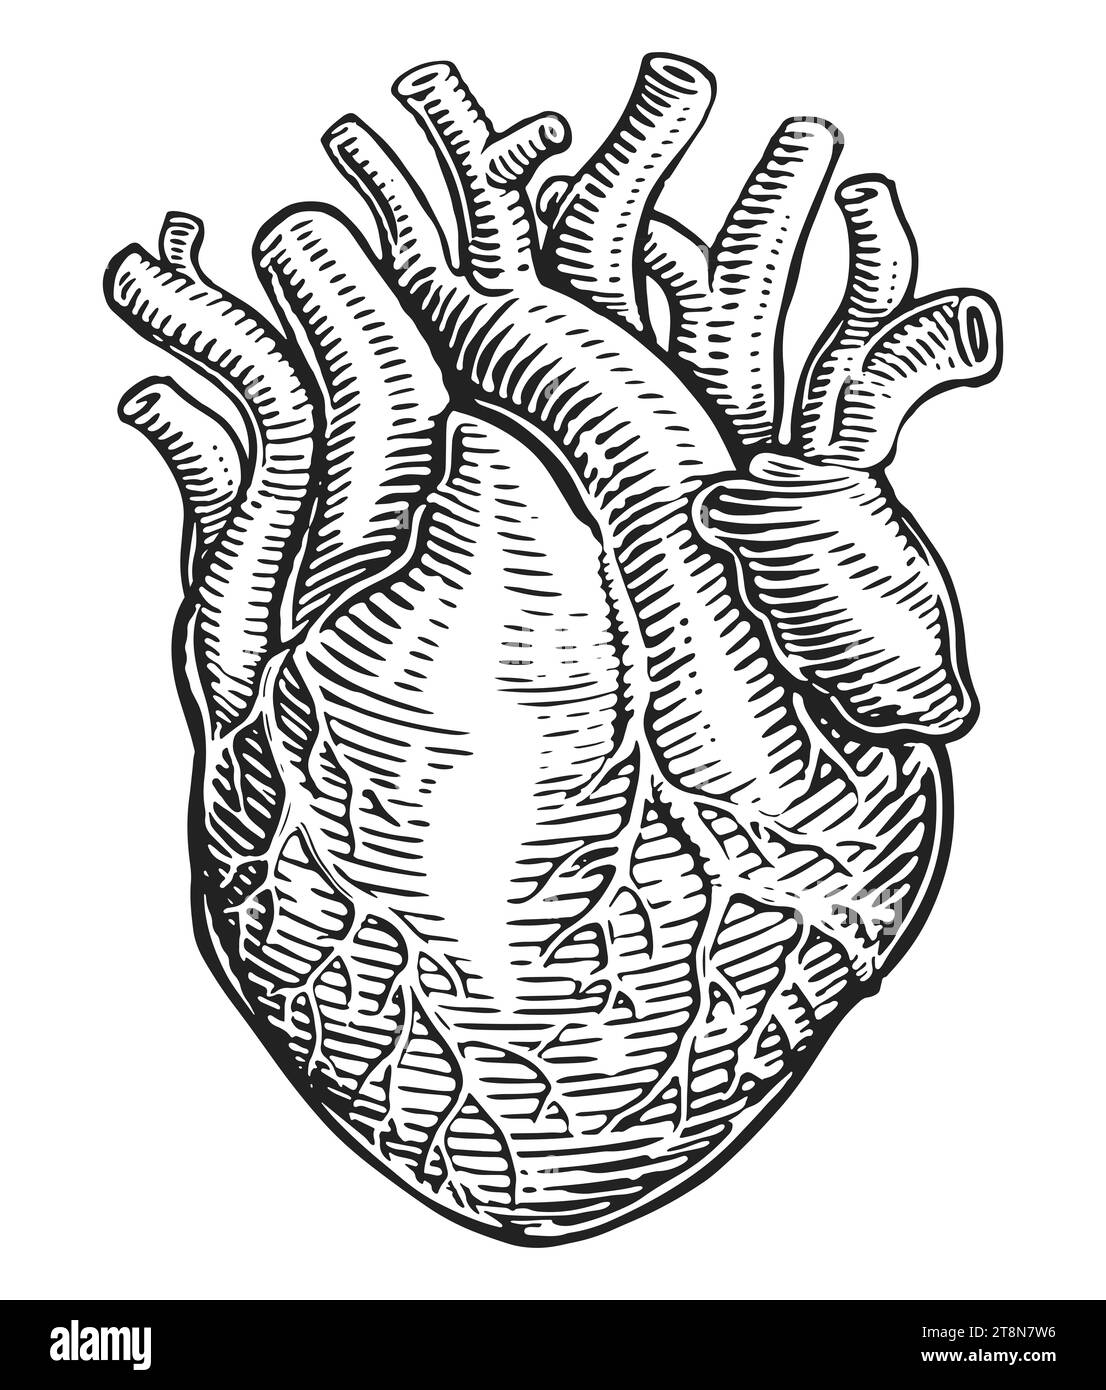

RF2T8N7W6–Muscle cardiaque humain dessiné à la main et vaisseaux sanguins dans le style de gravure vintage. Anatomie, illustration d'esquisse

RF2WC5NT4–Coeur humain avec des veines, croquis isolé sur fond blanc. Illustration vectorielle dessinée à la main dans le style de gravure vintage